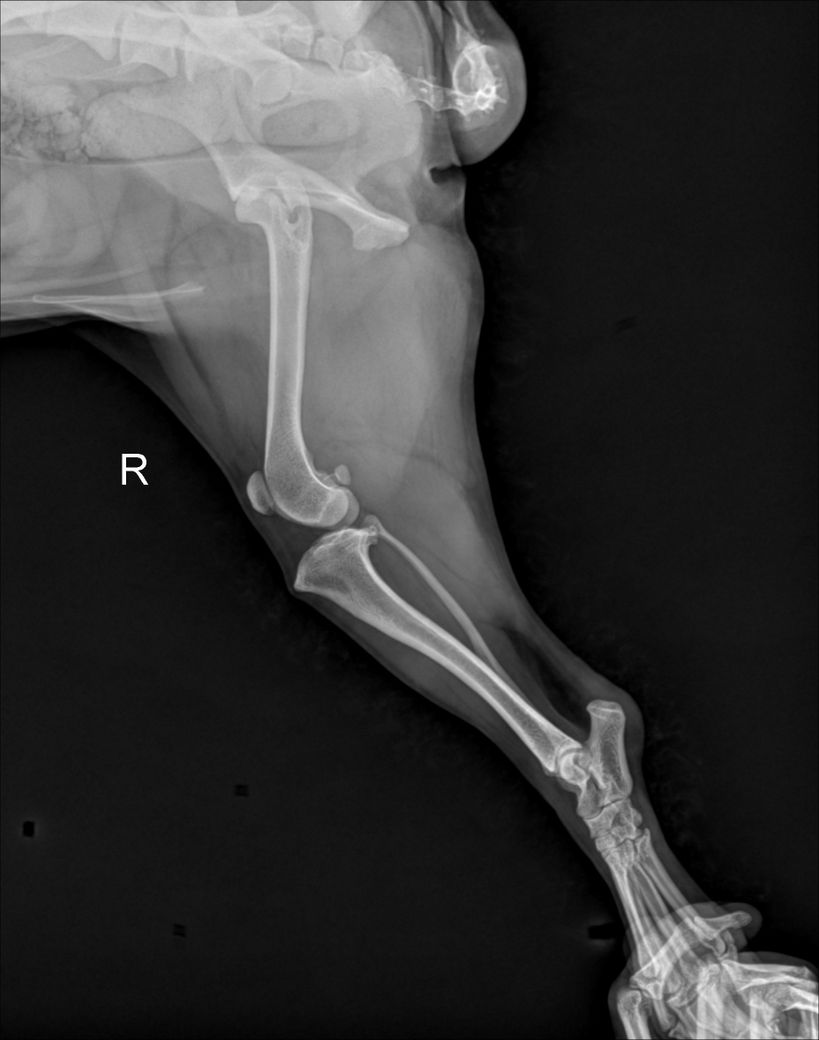

제시된 사진에서는 우측 슬과절 관절낭의 종창 즉, 물이 찬 현상이 있습니다. 이런 현상이 일어나는 원인에는 인대의 문제일 수도 있고, 면역계통의 문제일 수도 있습니다. 특히 이런 물이 찬 상태는 개에서는 십자인대가 손상이 있을때 나타나는 주요 현상으로 스테로이드와 같은 소염작용이 있는 약물을 투약하면 일시적으로 개선될 수 있습니다. 다만 십자인대가 점차 뻣뻣해지면서 향후 십자인대 단열이 발생할 가능성이 높아지니 TPL을 낮추는 수술을 선행적으로 해줄 필요가 있습니다.

사진상에서 실제 좌측에 비해 우측의 TPL이 증가한 양상이 명확하게 관찰되니 주치의와 상담 후 TPLO 고려하시기 바랍니다. ㅈ